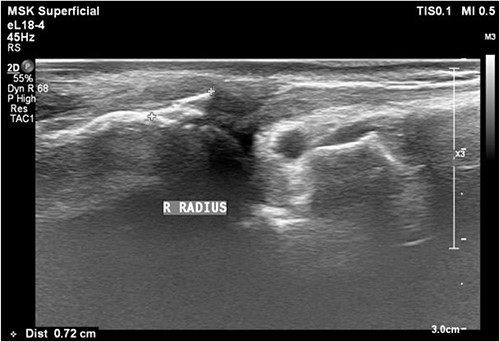

A 35-year-old male with no significant medical history fell from a third-floor balcony while working in February 2022, resulting in a right distal radius fracture that was treated with volar plate fixation. However, during an outpatient visit in November 2022, he reported a right thumb weakness that had been present for 3–4 months. Right wrist X-ray showed fracture at distal radius and carpal bones, s/p internal fixation (Fig. 5). A sonogram revealed a right thumb flexor tendon injury (Fig. 6), and he was admitted to our orthopedic ward for surgical repair of the FPL rupture on 12 November 2022. During the operation, plastic surgeon was consulted to repair the FPL rupture with a PL graft, repair the radial artery rupture and vessel with graft, repair the carpal ligament with left tensor fascia lata, release scar contracture of the volar and dorsal carpal region, and perform neurolysis of the median nerve due to adhesion to the FPL tendon.

Sonogram of the right thumb showing an injured flexor tendon. Asymmetric fibrillar structures of the right FPL tendon were observed.